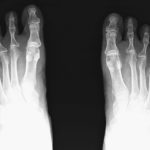

- Röntgen Füße bds dp initiales rechts CRPS

- Vorfuß Röntgen im Stehen, unter Belastung Krallenzehen / Hammerzehen